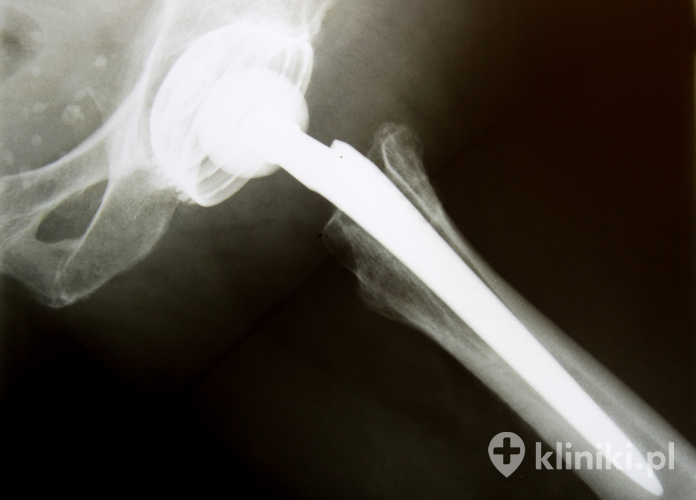

Endoprotezoplastyka stawu biodrowego polega na wymianie całości lub części tworzących go struktur. W przypadku wymiany obu elementów, tworzących staw biodrowy (głowa i panewka), mówimy o endoprotezoplastyce całkowitej. Jeżeli wymianie podlega tylko jeden element (głowa kości udowej) jest to endoprotezoplastyka częściowa, zwana również połowiczą. Każda z tych operacji ma swoje określone wskazania.

Całkowita endoprotezoplastyka biodra polega na wymianie panewki i głowy kości udowej, natomiast częściowa obejmuje jedynie głowę kości udowej

W przypadku tego zabiegu wymianie podlega tylko głowa i część szyjki kości udowej, panewka stawu pozostaje nienaruszona. W związku z tym dochodzi do kontaktu sztucznej powierzchni wszczepionej protezy z naturalną, chrzęstną powierzchnią panewki stawowej. Może to z czasem powodować powstawanie zmian w obrębie panewki.